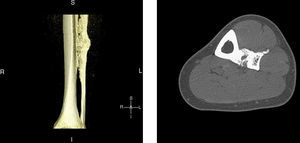

Clinical presentationA 42-year-old male with no prior history presented 3 months prior to his coming to our department with continuous pain in the middle third of the left leg. Upon examination there was selective pain on palpation on the mid third of the left tibia. No skin atrophy or deformity of the affected limb was detected. Laboratory analysis, including acute phase reactants, complete blood count, blood chemistry, bone remodeling markers in blood and urine, thyroid hormone and proteins, were normal. A simple X-ray of the left leg (Fig. 1) presented an image of hyperostosis with a thickened cortex on the mid third of the tibia and peroneus, extending along the bone and showing a “dripping candlewax” image. A bone scan with 99Tc (Fig. 2) observed an increase in uptake. A computerized tomography (Fig. 3a and b), showed dense cortical hyperostosis of the distal half of the tibial and peroneal diaphysis, with wavy and exhuberant borders, cortical sclerosis and periostic and endostic thickening, predominantly on the lateral tibia and mid peroneal, with a “dripping candlewax” aspect, suggestive of melorheostosis.

3D sagittal reconstruction, computerized tomography of the left leg: the distal half of the tibial and peroneal diaphysis shows dense cortical hyperostosis with wavy and exhuberant borders and associated periosteal and endosteal thickening, predominantly on the lateral tibia and medial fibula, giving an image of “dripping candlewax”, suggestive of melorheostosis.